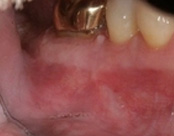

The patient was eating and bit down, felt and heard a “pop.” The tooth had cracked in the middle of the root. The tooth helps hold the patients partial in place and did not want to lose the tooth. The crack was removed with the laser and then restored.

The photograph is 2 months after the crack repair. The area looks like nothing was done (no redness, no scarring, etc.) and the tooth is there helping to hold the partial denture.